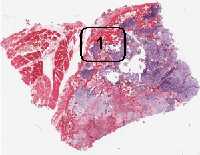

On the histologic slide, this tumor is composed of a low-grade

neoplastic chondroid of low cellularity. The overall cytologic

features are reminiscent of normal cartilage but they are separated

into numerous lobules separated by thin fibrovascular bands.

These lobules can vary from one to several millimeters in diameter.

The tumor bulge out and disrupted the cortical bone.

In another location of the tumor, there is definitive

invasion

of the haversian system. This is an important features for the